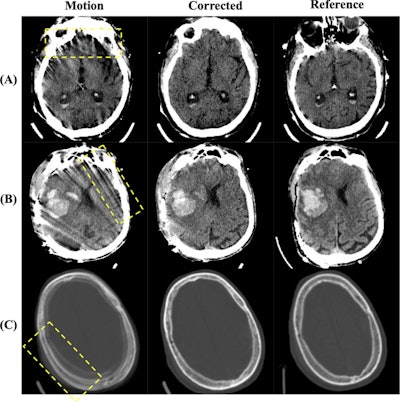

Visual examples of image quality improvements. (A) and (B) show corrections of motion artifacts within the brain tissue, where (A) corrects the star-like artifacts originating from the skull and (B) corrects the severe streaking artifacts across the brain. (C) shows the removal of a "double skull" artifact caused by substantial head motion. Image display window is [0,80]HU for (A) and (B) and [−500, 1500]HU for (C). Images and caption courtesy of Academic Radiology.